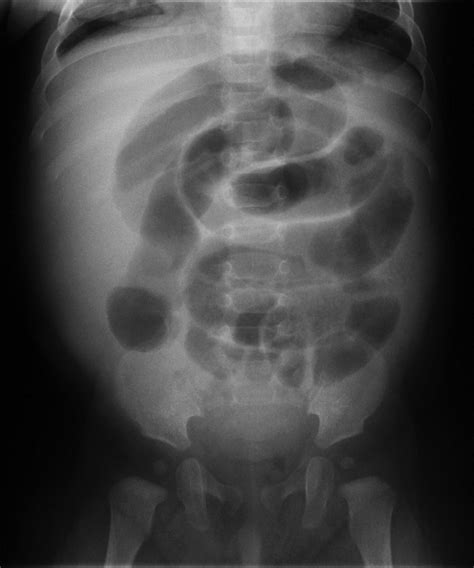

Intussusception is a serious medical condition that occurs when one segment of the intestine slides into another, causing a blockage. This condition is most common in infants and young children but can also affect adults. Early and accurate diagnosis is crucial for effective treatment. One of the primary diagnostic tools used for detecting intussusception is the ultrasound of intussusception. This non-invasive imaging technique provides valuable insights into the condition, helping healthcare professionals make informed decisions.

Intussusception is a medical emergency that requires immediate attention. It occurs when a segment of the intestine, known as the intussusceptum, telescopes into an adjacent segment, called the intussuscipiens. This can lead to obstruction, ischemia, and potentially necrosis of the affected bowel. The condition is more prevalent in children, particularly those between 3 months and 3 years old, but it can also occur in adults, often due to underlying conditions such as tumors or polyps.

An ultrasound of intussusception is a critical diagnostic tool that provides real-time images of the abdomen. This imaging technique uses high-frequency sound waves to create detailed images of the internal structures, making it an effective method for detecting intussusception. Ultrasound is particularly useful because it is non-invasive, does not involve radiation, and can be performed quickly and efficiently.